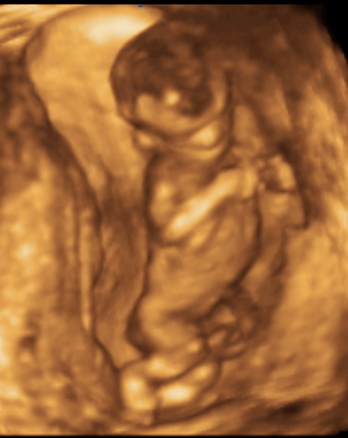

A doktor bácsi szerint annyira szépek és fejlettek vagyunk, (45 cm és 2 kg, pedig beteg voltam amiatt visszafogyott kicsit) nomeg egy hete szépen befordultunk és illeszkedtünk kb 6 hetünk van vissza (néha bizony eléggé feszíti szét a medencecsontom, mondom is neki, hogy kis Pockom még van időd, nyugi legyen, anya egyébként is be van sz... rendesen a szülés miatt) . Tehát valszeg a kiscsaj május végén meglesz.